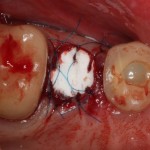

Снимаем коронки, готовим зубы к удалению:

Начинаем с самого сложного — зуба #47:

Гранулема настолько большая, что ее видно из лунки:

Аккуратно ее удаляем. Приходится пожертвовать межкорневой перегородкой:

В лунку помещаем Neocones, Bioss Collagen:

Затем к краям лунки подшивается Mucograft Seal:

Это относительно новый форм-фактор Geistlich Mucograft, специально предназначенный для таких случаев:

После чего можно заняться лункой зуба #45. Там тоже гранулема. Немаленькая:

Которую мы удаляем, а саму лунку консервируем точно по такому же принципу, что и лунку #47 (Neocones, Bioss Collagen):

И «запечатываем» с помощью Mucograft Seal: